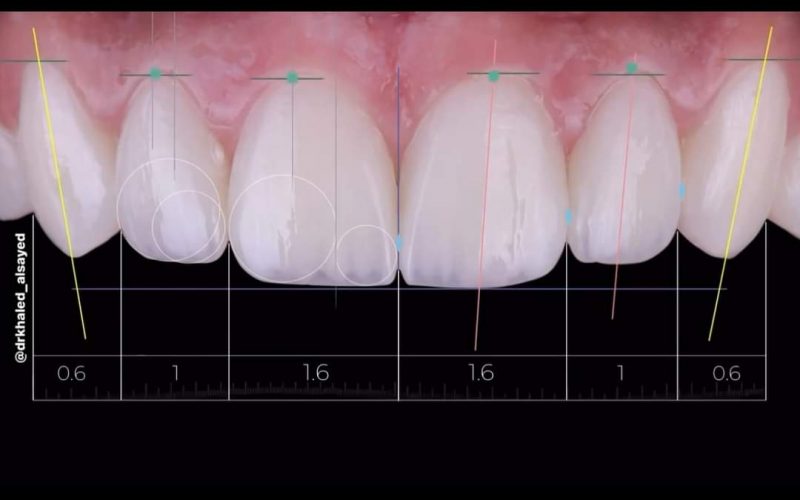

Veneers

Custom-made veneers are a perfect solution to cover discoloration, gaps, or chips. We offer thin, durable shells that transform your smile with a natural and lasting finish.